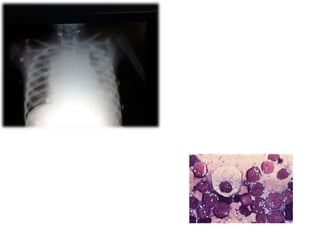

• 6.

Leukemia • the onlyavailable treatment for leukemia was blood transfusion. Patients never benefitted from a remission and died within a few months. • The development of multiple-agent chemotherapy for induction, consolidation and maintenance, CNS prophylaxis and supportive care ushered in a new era of cure for patients with leukemia.